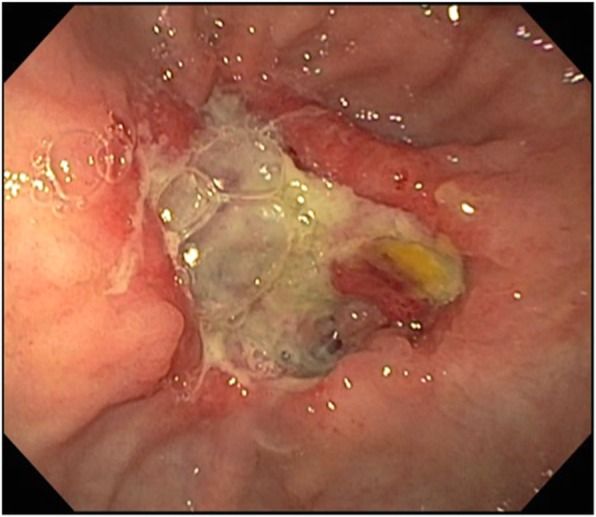

Для купирования гидропневмоторакса проведено дренирование левой плевральной полости. При эндоскопическом исследовании подтверждена перфорация пищевода в его нижней трети, близко к области пищеводно-желудочного перехода, — дефект составлял 30% окружности пищевода и имел длину более 4 см (рис. 3 — A). Кроме того, было обнаружено большое количество пищи и жидкости в желудке и язвенный дефект в препилорическом отделе (рис. 2), который потребовал выполнения биопсии.

Рисунок 2 [2].

Рисунок 3. Серия эндоскопическихобследований перфорации пищевода (эндофото) [2]А. Первая ЭГДС: обширный дефект пищеводной стенки, визуализируются средостение и перикард.

B. ЭГДС после удаления пищеводного стента: наблюдается заживление дефекта с образованием грануляционной ткани.

С. Полное заживление перфорации.

Впоследствии пищеводный стент был удален (рис. 3 — B, C), пациент переведен в учреждение сестринского ухода. В настоящее время лечение продолжается. Состояние пациента оценивается как стабильное.